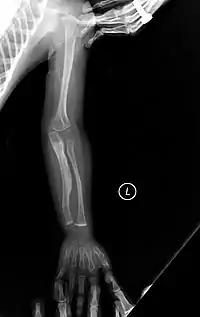

- يولدون بكسور متعددة وتبين الأشعة السينية التأم بعض الكسور أثناء مراحل نمو الجنين داخل رحم الأم.

عند التشخيص يتم ملاحظة الأعراض المرافقة ويتم أخذ عينة من الجلد لإجراء الفحوصات على الكولاجين، أيضاً تؤخذ عينة دم لإجراء الفحوصات والتحاليل على دي ان اي ( DNA). يتم تشخيص العظام في معظم الحالات عن طريق الأشعة السينية.